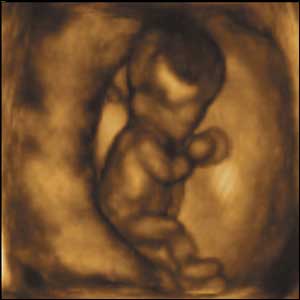

22 týdnů, 21 cm

Ve 22 týdnech jsou děti schopny jemných pohybů rukou a prsty. Na krátkou chvíli se pozorované dítě škrámalo, mnulo a dotýkalo brady a nosu.